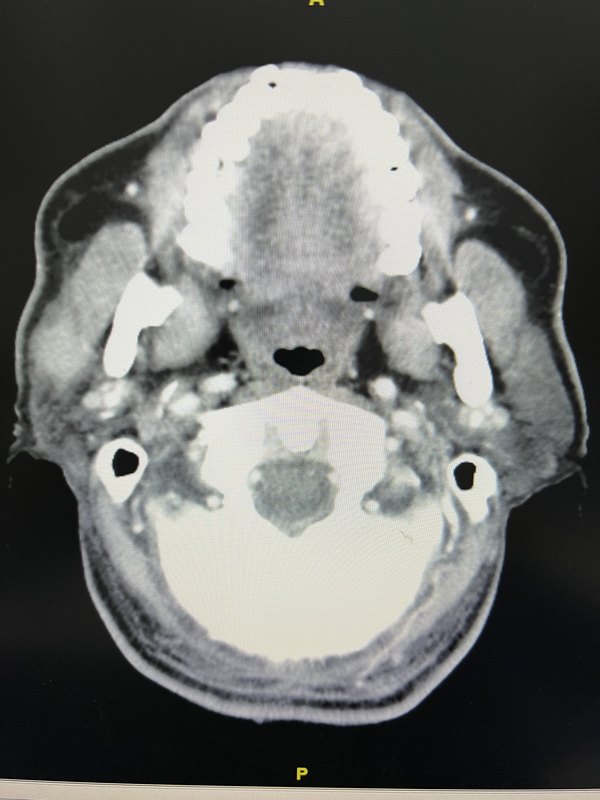

腮腺腺泡細胞癌(Acinic?cell?carcinama)是臨床比較少見的一種惡性腫瘤。約占唾液腺腫瘤的3%左右,男女發(fā)病比例約3:1。臨床具有如下特點:1)?好發(fā)于腮腺淺葉,多為單側發(fā)病,患者常有較長的病史;2)?多為無痛性腫塊,淋巴結轉移率低,約為3%~9%。3)?大部分腫瘤具有包膜,與周圍正常腮腺組織分界尚清晰,故容易與腮腺良性腫瘤混淆。4)?CT上腫瘤呈稍低密度或等密度,鈣化少見;MRI上病灶呈等T1、混雜長T2信號,密度、信號多不均勻。治療上,臨床根據腫瘤的位置決定手術方式,位于淺葉者,行腮腺淺葉全切除+面神經解剖術;如位于深葉則應行腮腺全切除術,如腫瘤侵犯面神經,受累的神經應一并切除并行面神經重建術。腺泡細胞癌預后較好,5年生存率約為90%。